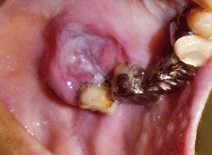

図❶ 下顎左側小臼歯部、歯肉頬移行部粘膜

口腔内所見:下顎左側小臼歯部、歯肉頬移行部粘膜(図❶)と上顎左側大臼歯部の口蓋側粘膜(図❷)に、発赤を伴った潰瘍形成を認めた。